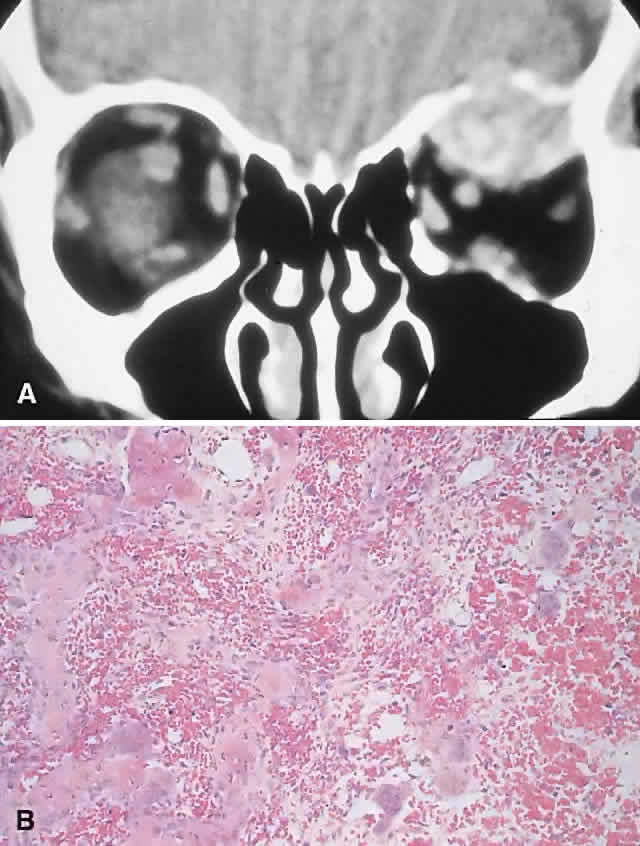

The radiologic and histologic appearances are essentially the same as for GCG (Fig. 8). Treatment of the hyperparathyroidism often results in spontaneous resorption and healing of the bony lesion.12,105,108 Hence, a careful clinical evaluation for manifestations of hypercalcemia or renal dysfunction may obviate the need for surgery.

Fig. 8. A 69-year-old woman with acutely painful left proptosis for 2 days. Examination showed left preseptal edema associated with 9 mm of proptosis and 7 mm of inferior displacement. A. CT showed a well-defined, mottled superior orbital mass with erosion of the roof. B. Histology demonstrated hemorrhage associated with numerous osteoclastic giant cells, in addition to new bone formation (hematoxylin-eosin, × 50).